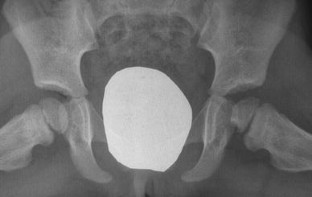

Inflammatory or septic arthritis due to Mp is an extremely unusual manifestation in children, and the functional outcome of the joints is difficult to be predicted. Two cases with Mp infection are presented. The first patient had positive PCR for Mp after hip aspiration and arthrotomy with thorough irrigation and debridement. A flattened femoral head was detected during the follow-up, which became quite spherical a year after. An arthrotomy with medial synovectomy of the knee was performed in the second patient. Lack of full knee extension was presented during the first 3 months, which gradually decreased to 7° in the final follow-up. The suspicion of Mp infection with extra-pulmonary involvement in children is mainly based on clinical, epidemiological and radiological data, but laboratory testing is required for confirmation. Rapid diagnosis of probability consists of serum tests, and their results are essential for early therapeutic planning. The direct diagnosis of Mp DNA through polymerase chain reaction (PCR) provides specificity and sensitivity. Very few cases of arthritis associated with Mp infection have been published but not with the severity of our cases. Clinical suspicion of Mp infection is of great importance, and the outcome depends on early diagnosis and specific treatment.